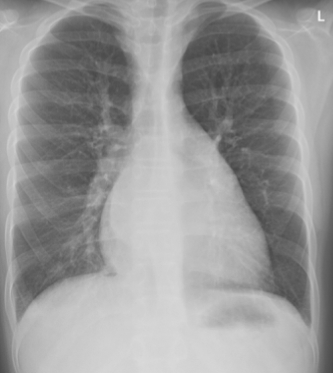

①胸部X线:心影多呈普遍性扩大,肺纹理增多,肺门或肺门附近阴影增加,肺部淤血